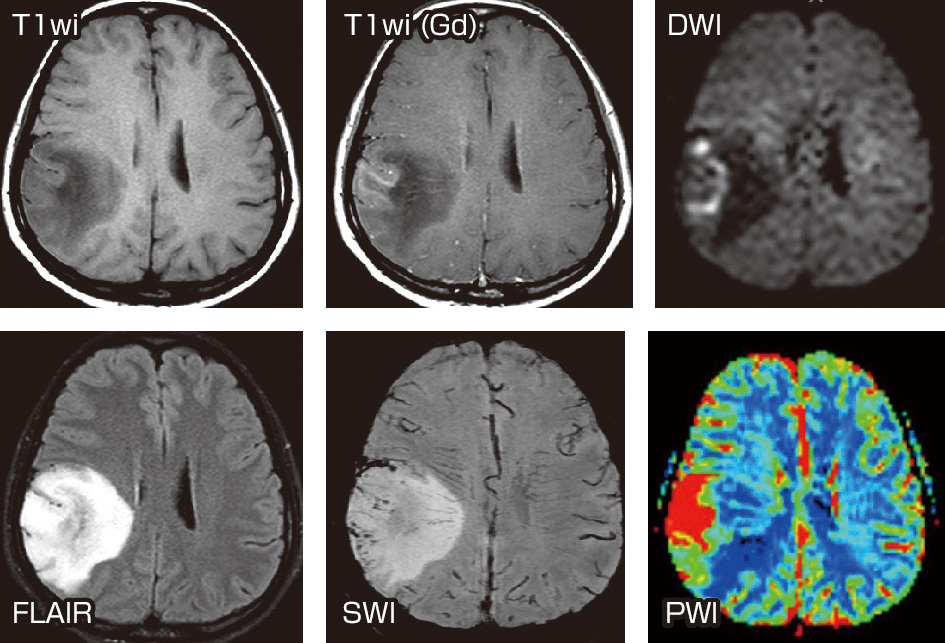

朝倉書店『内科学』(第12版)デジタル付録, 頭蓋骨腫瘍 skull tumor | 脳外科医 澤村豊のホームページ,

頭蓋骨腫瘍 skull tumor | 脳外科医 澤村豊のホームページ,[A11078202]リハビリテーションプログラムの手引書―身体障害の評価のために [単行本] B.C.ABREU; 矢崎 潔